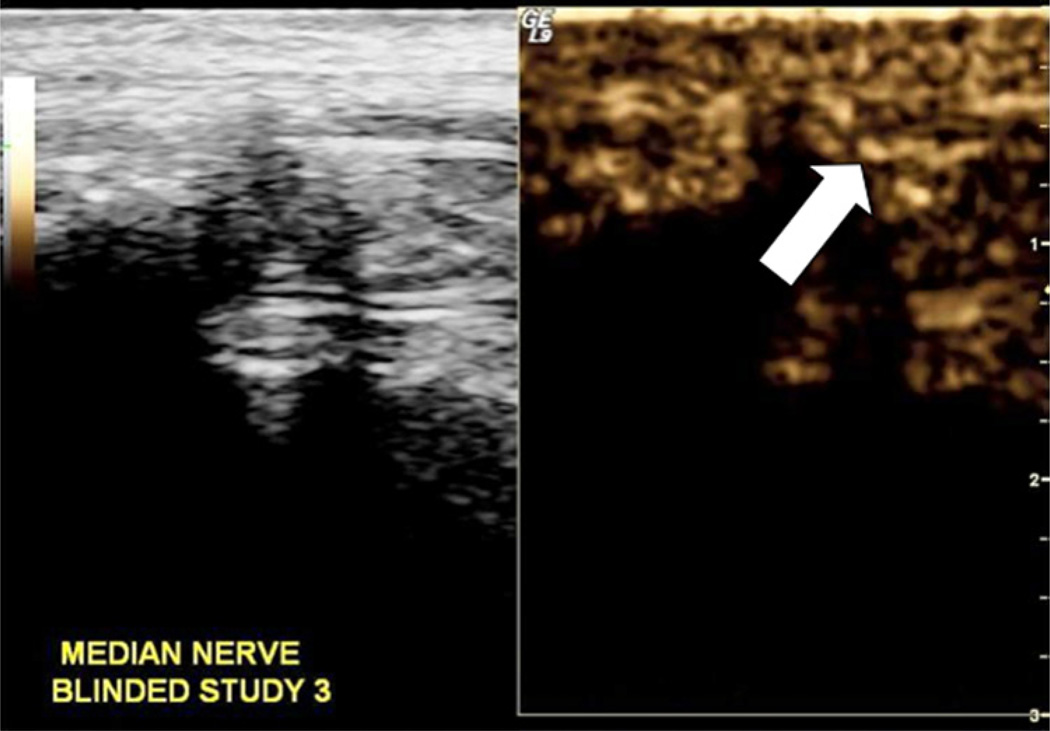

Description:This preclinical study was conducted to develop discrete sonographic instrumentation settings and also safe contrast dosing that would consistently demonstrate perineural vascularity along the median nerve. This set of imaging studies was conducted with a convenience cohort of young adult female monkeys (|). Sonographic equipment settings and dosing were refined throughout the imaging series to ensure consistent contrast-enhanced ultrasound imaging. A mechanical index of 0.13 was consistently used for imaging. Perineural vessels were imaged with a suspension solution of 0.04 mL Definity/0.96 mL saline introduced over 5 minutes for a total dose of 0.8 mL of contrast solution. Blinded studies of high and low dose contrast, along with saline injections, were correctly identified by two experienced sonographers. This preclinical study established adequate equipment settings and dosing that allowed for a valid demonstration of vascularity surrounding the median nerve.